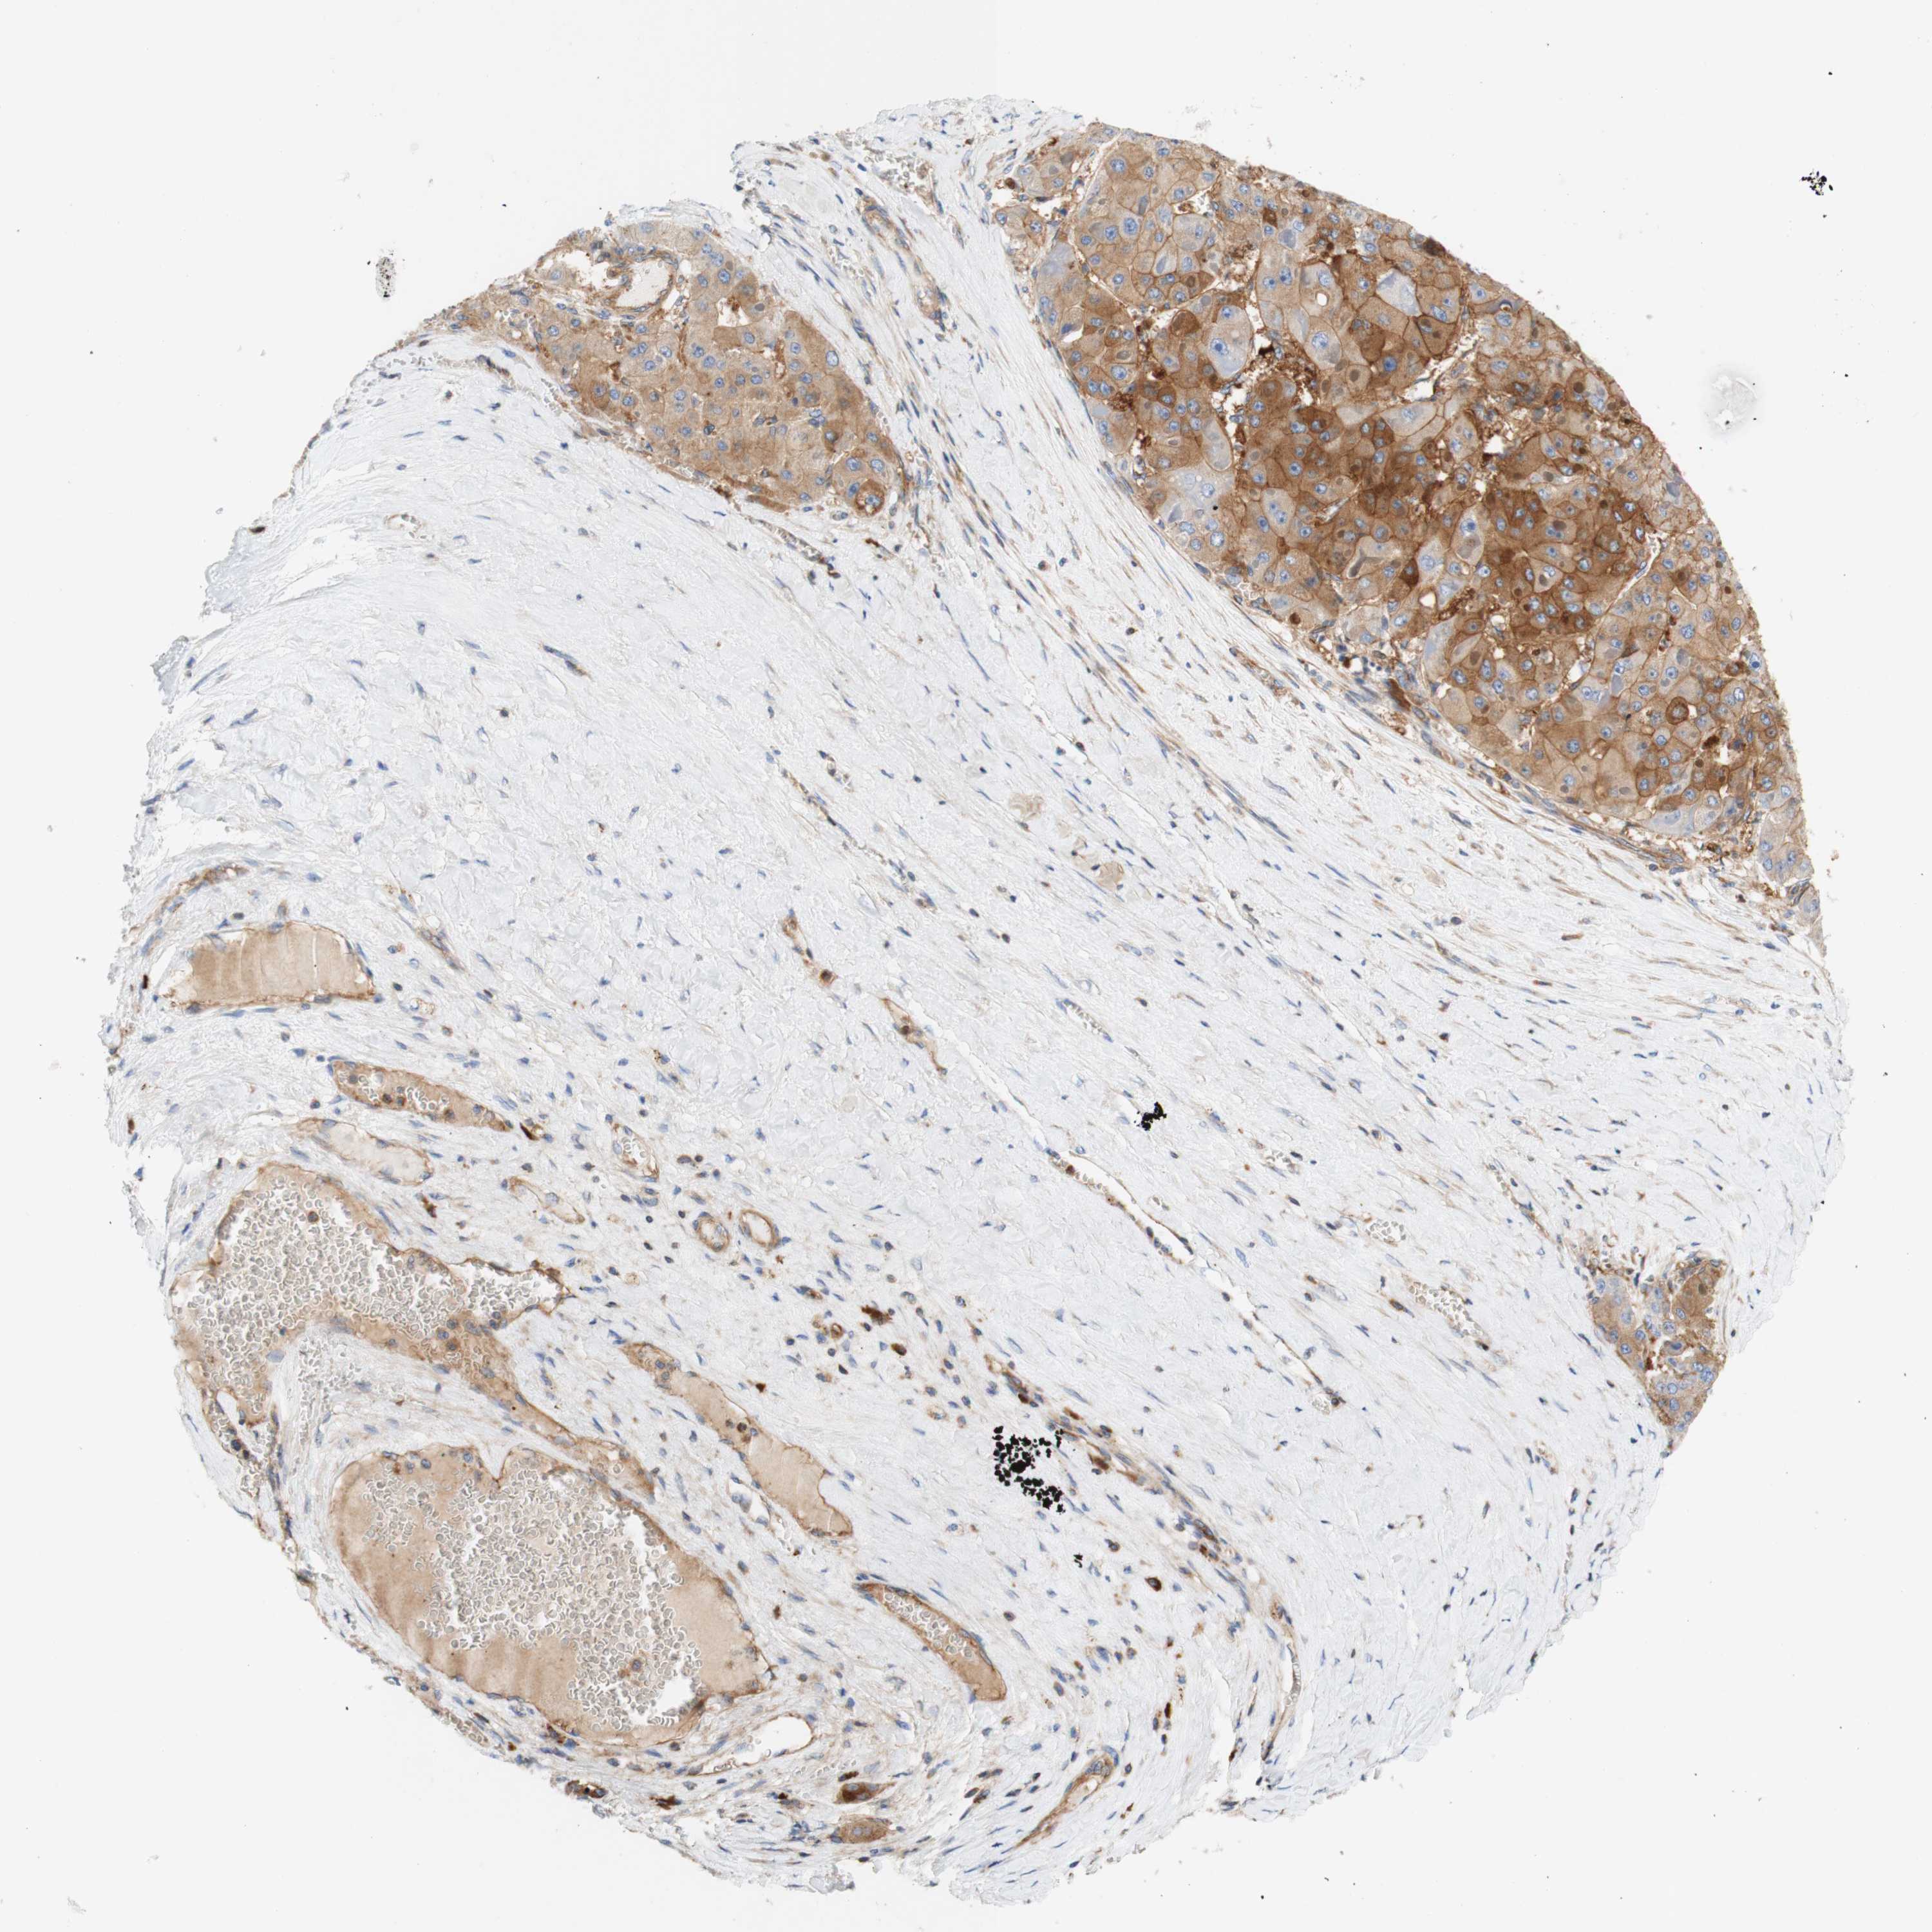

LIVER CANCER - Protein expressioni

A mouse-over function shows sample information and annotation data. Click on an image to view it in a full screen mode. Samples can be filtered based on level of antibody staining by selecting one or several of the following categories: high, medium, low and not detected. The assay and annotation is described here.

Note that samples used for immunohistochemistry by the Human Protein Atlas do not correspond to samples in the TCGA dataset.

Antibody stainingi

Antibody staining in the annotated cell types in the current human tissue is reported as not detected, low, medium, or high, based on conventional immunohistochemistry profiling in selected tissues. This score is based on the combination of the staining intensity and fraction of stained cells.

Each image is clickable and will lead to virtual microscopy that enables deeper exploration of all samples and also displays staining intensity scores, fraction scores and subcellular localization as well as patient and tissue information for each sample.

Antibody HPA010961

Antibody HPA011419

Staining

High

Medium

Low

Not detected

Intensity

Strong

Moderate

Weak

Negative

Quantity

>75%

75%-25%

<25%

None

Location

Nuclear

Cytoplasmic/membranous

Cytoplasmic/membranous,nuclear

Cholangiocarcinoma

Carcinoma, Hepatocellular, NOS